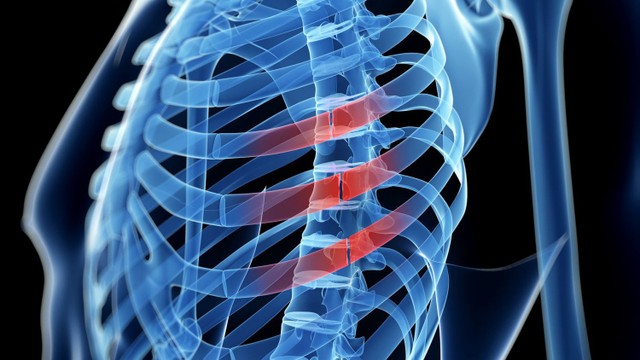

:format(webp)/ran_xuong_suon_bao_lau_thi_khoi_0_b153ec53ab.jpg)

Nhiều người không khỏi thắc mắc liệu rạn xương sườn bao lâu thì khỏi? Theo các chuyên gia, thời gian điều trị rạn xương sườn thường phụ thuộc vào nhiều yếu tố khác nhau và không đồng nhất ở mỗi người. Cùng tìm hiểu bài viết sau để hiểu rõ hơn về tình trạng rạn xương sườn nhé!